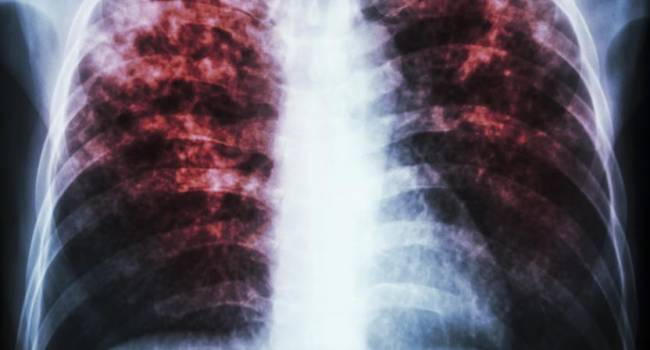

En 2021 Guanajuato registró 373 casos de tuberculosis

Entre los síntomas de esta enfermedad destaca la desnutrición, la fiebre vespertina, la vulnerabilidad y marginación, además que los fumadores, personas con diabetes, con VIH, pueden ser propensos a esta enfermedad, por lo que es a la población que más se debe cuidar.